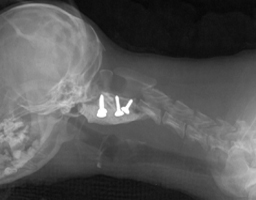

TTA |

TPLO |

MMP |